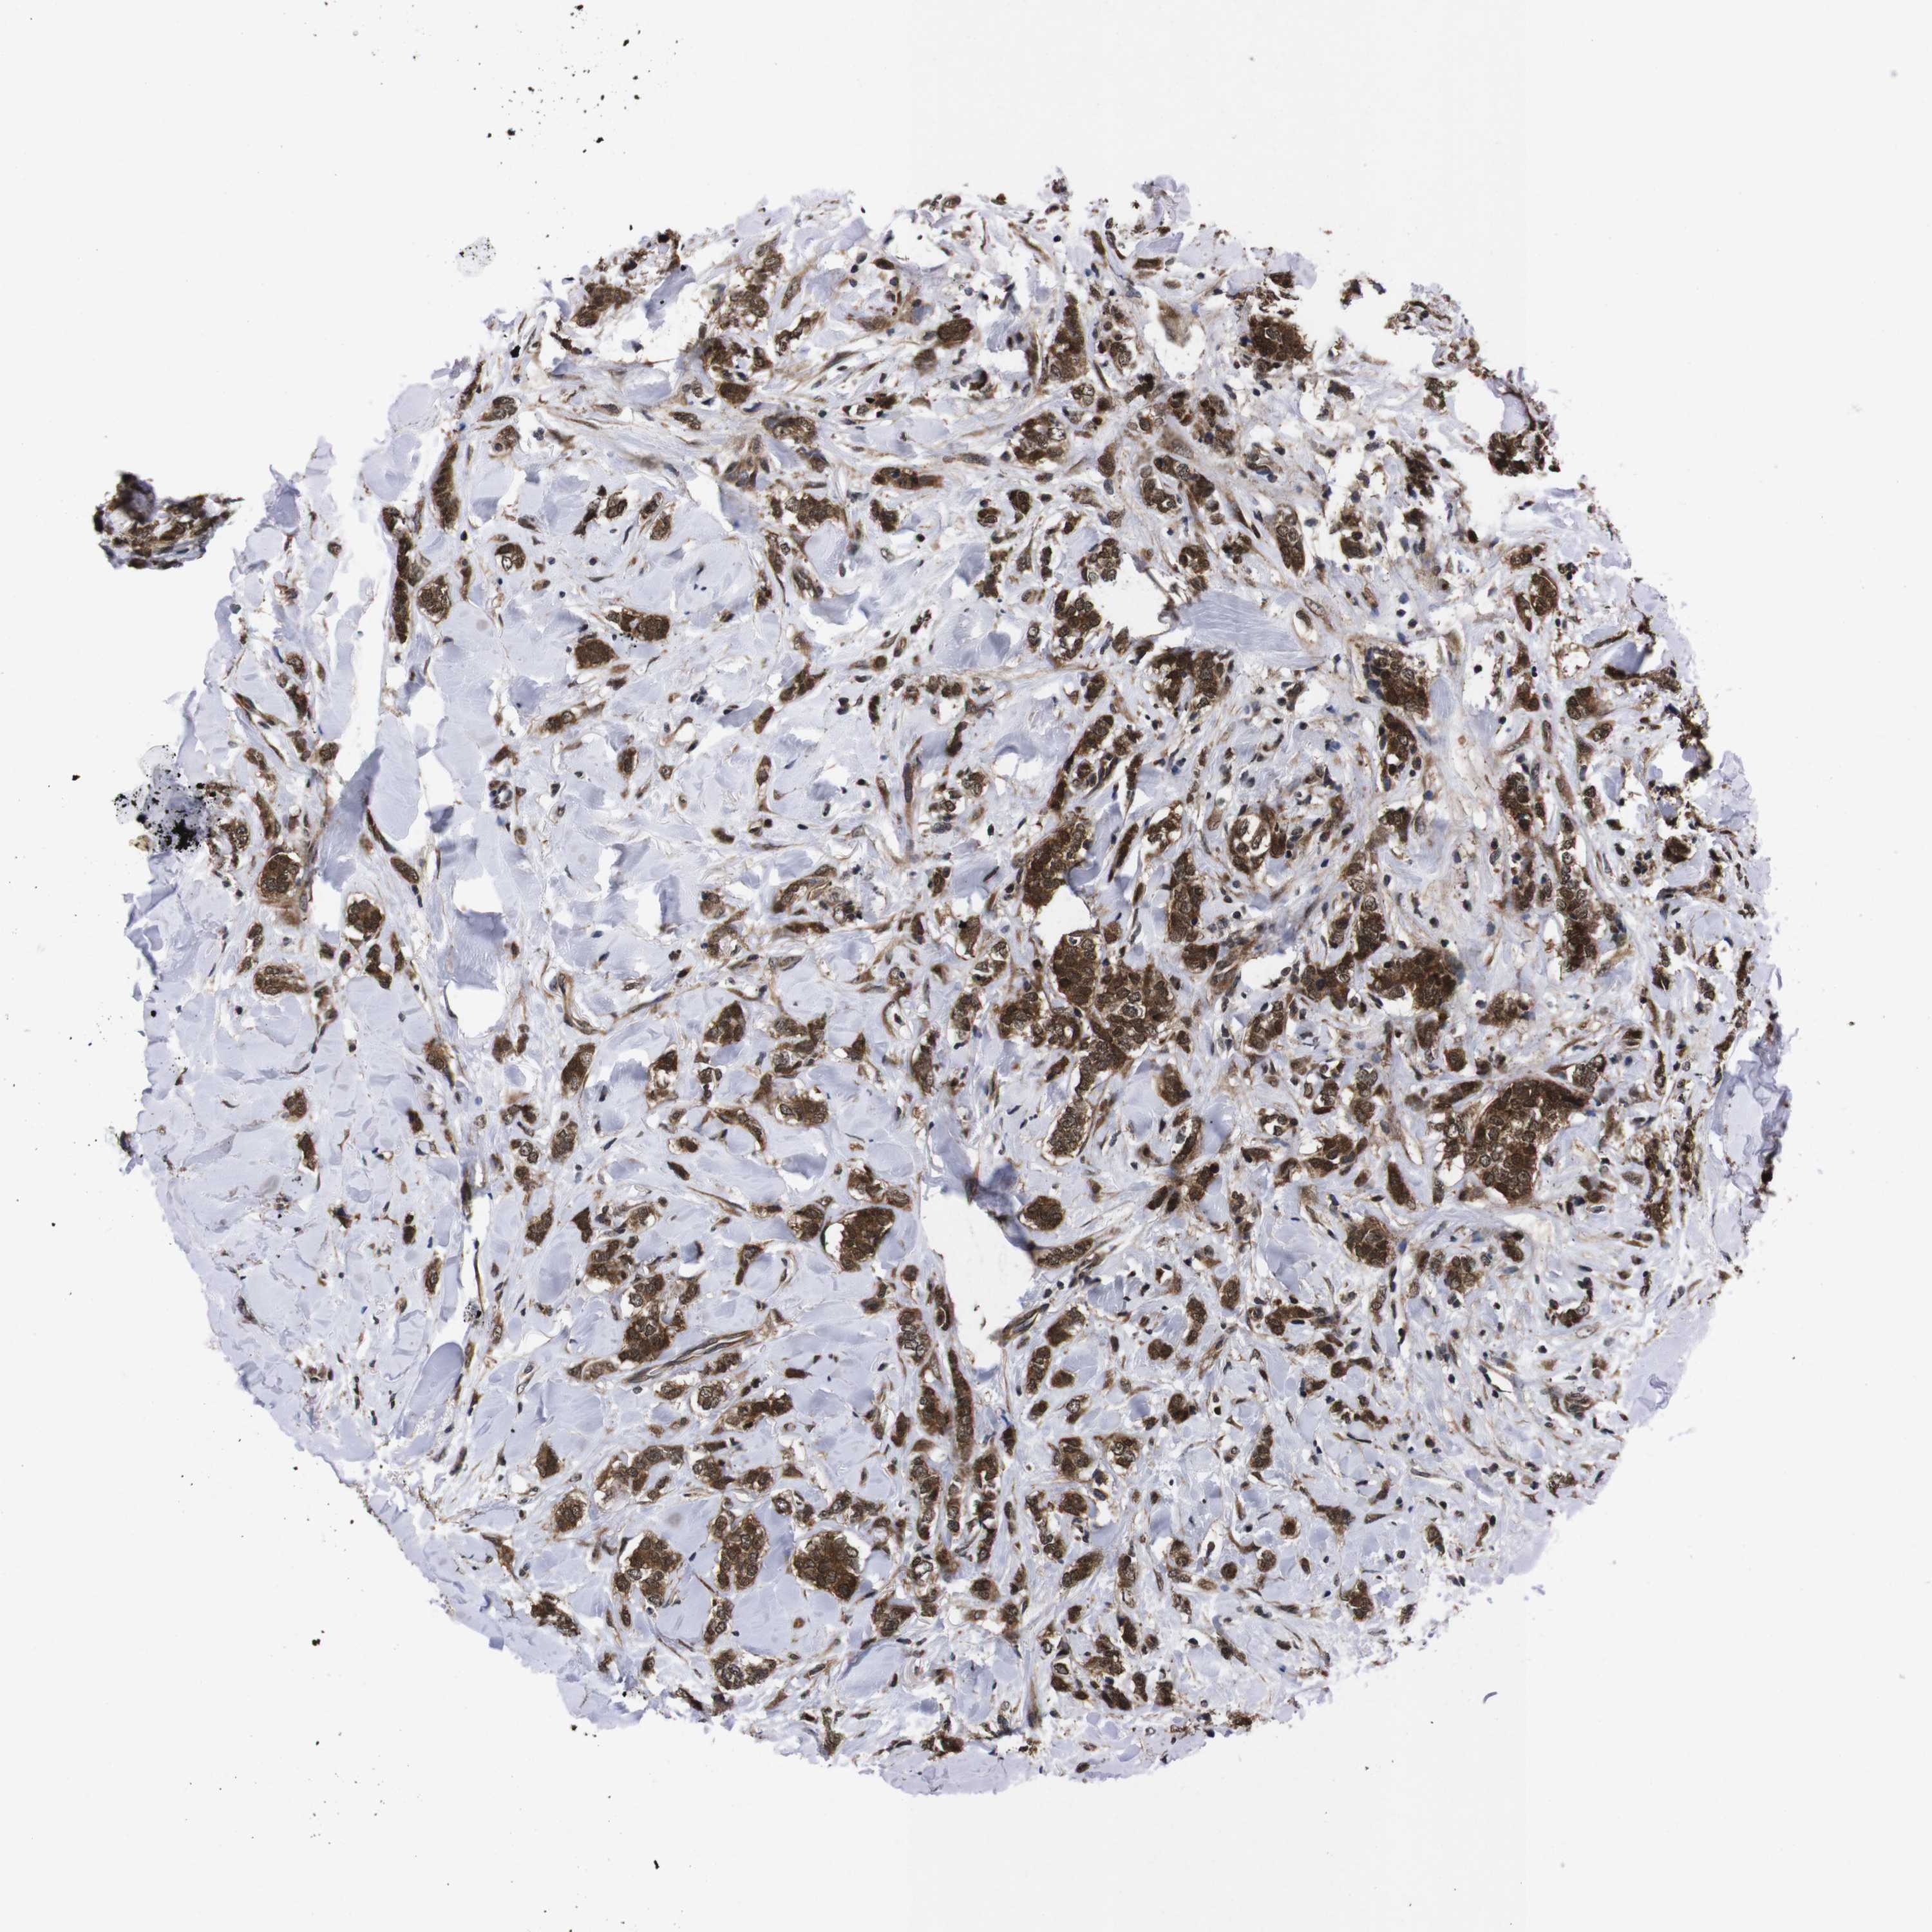

BRCA TCGA BRCA VALIDATION PROTEIN EXPRESSION